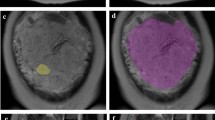

This retrospective study includes 99 pregnant women with pathologically confirmed placental invasion and 56 pregnant women with simple placenta previa. All participants underwent magnetic resonance imaging after 24 gestational weeks. The placenta was segmented in sagittal images from both turbo spin echo (TSE) and balanced turbo field echo (bTFE) sequences. Textural features were extracted from the both original and Laplacian of Gaussian (LoG)-filtered MRI images. An automated machine learning algorithm was applied to the extracted feature sets to obtain the optimal preprocessing steps, classification algorithm, and corresponding hyper-parameters.